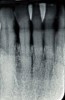

During the 1970s, researchers began investigating the causative nature of periodontal diseases. Dogma of the time suggested that periodontal disease was caused by mechanical irritants such as calculus. It was also believed that lipopolysaccharides or endotoxins derived from gram-negative bacteria were deeply embedded in the cementum.6,7 Treatment for periodontal inflammation was based on thoroughly removing calculus and rough cementum from tooth structures and planing root surfaces to a glassy-smooth texture.8 The “glassy-smooth” therapy endpoint often led to hourglass-shaped roots (Figure 1), hypersensitivity for the patient, and the occasional pulpal exposure.9

Figure 1  The “glassy-smooth” therapy endpoint often led to hourglass-shaped roots.